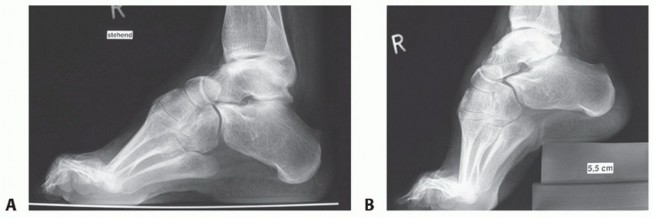

FIG 2 • Conventional radiograph. A,B. Lateral view with and without correction of the forefoot equinus. (continued)*

Conventional Radiographs

Lateral view (standing) (FIG 2A) Posterior shift of the lateral malleolus

The longitudinal axis of the talus is parallel to the axis of the calcaneus.

The calcaneus seems to be shortened due to varus position.

There is decreased distance between the navicular and the medial malleolus.

The calcaneocuboid joint is visible; it is normally obscured by the talonavicular joint. The first metatarsal is plantarflexed and its head has a plantar prominence.

Claw toes

The posterior subtalar joint is projected horizontally. Opened sinus tarsi (“sinus tarsi window”)

Anteroposterior (AP) view (standing) (FIG 2B)

Longitudinal axes of the talus and calcaneus are parallel.

There is a medial shift of the talonavicular joint and, in some cases, the calcaneocuboid joint. The first metatarsal seems to be shortened due to its plantarflexed position.

There is overlapping of the metatarsal bones, especially the fourth and fifth.

AP view of the ankle joint (standing) (FIG 2C) Varus deformity of the ankle joint

Hindfoot varus